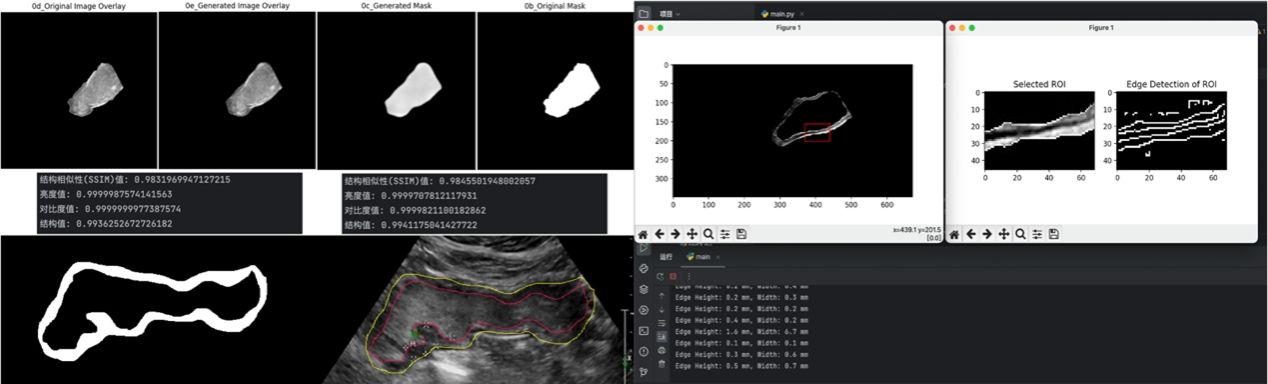

“智能胃超声”项目组由软件学院、国际信息与软件学院本科生丁铭泽、张鑫彦和殷莉钦组成,软件学院、国际信息与软件学院刘斌教授担任项目组的指导教师。项目组与中国医科大学附属盛京医院刘治军教授团队合作,围绕经腹胃超声及胃癌多模态影像,通过项目组自主探索的“UC-Net”神经网络模型,实现胃部超声区域的智能定位与胃壁厚度的自动测量。在世界卫生组织常规胃癌分型基础上,引入亚洲胃癌分型方案。此项目旨在提高胃超声在常规胃病筛查的使用比例与早期胃癌的检出率,改善患者胃部检查舒适度,力争为胃部超声检查专业人才的培养以及亚洲人群胃部疾病患者的诊治提供助力。